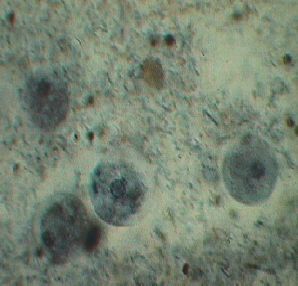

Es gibt kugelige, stäbchenförmige und schraubenförmige Bakterien.

gram negative Bakterien

Entamöba invadens